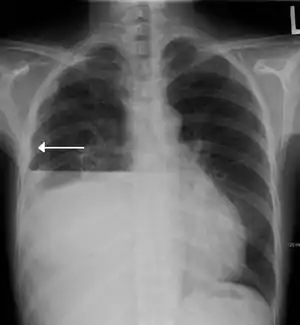

Hydropneumothorax is defined as the presence of both air and fluid within the pleural space.[1] An upright chest x-ray will show air fluid levels. The horizontal fluid level is usually well defined and extends across the whole length of one of the hemithorax.

| A hydropneumothorax with a white arrow pointing to the lung's pleura | |